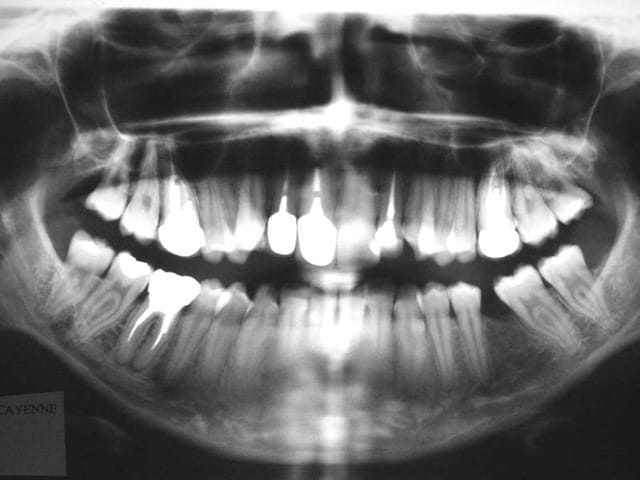

Voici les Rx. de début

notre ami Zorglub pourra ainsi nous faire part de

ses objectifs de TTT.

son plan de TTT.

et les justifier